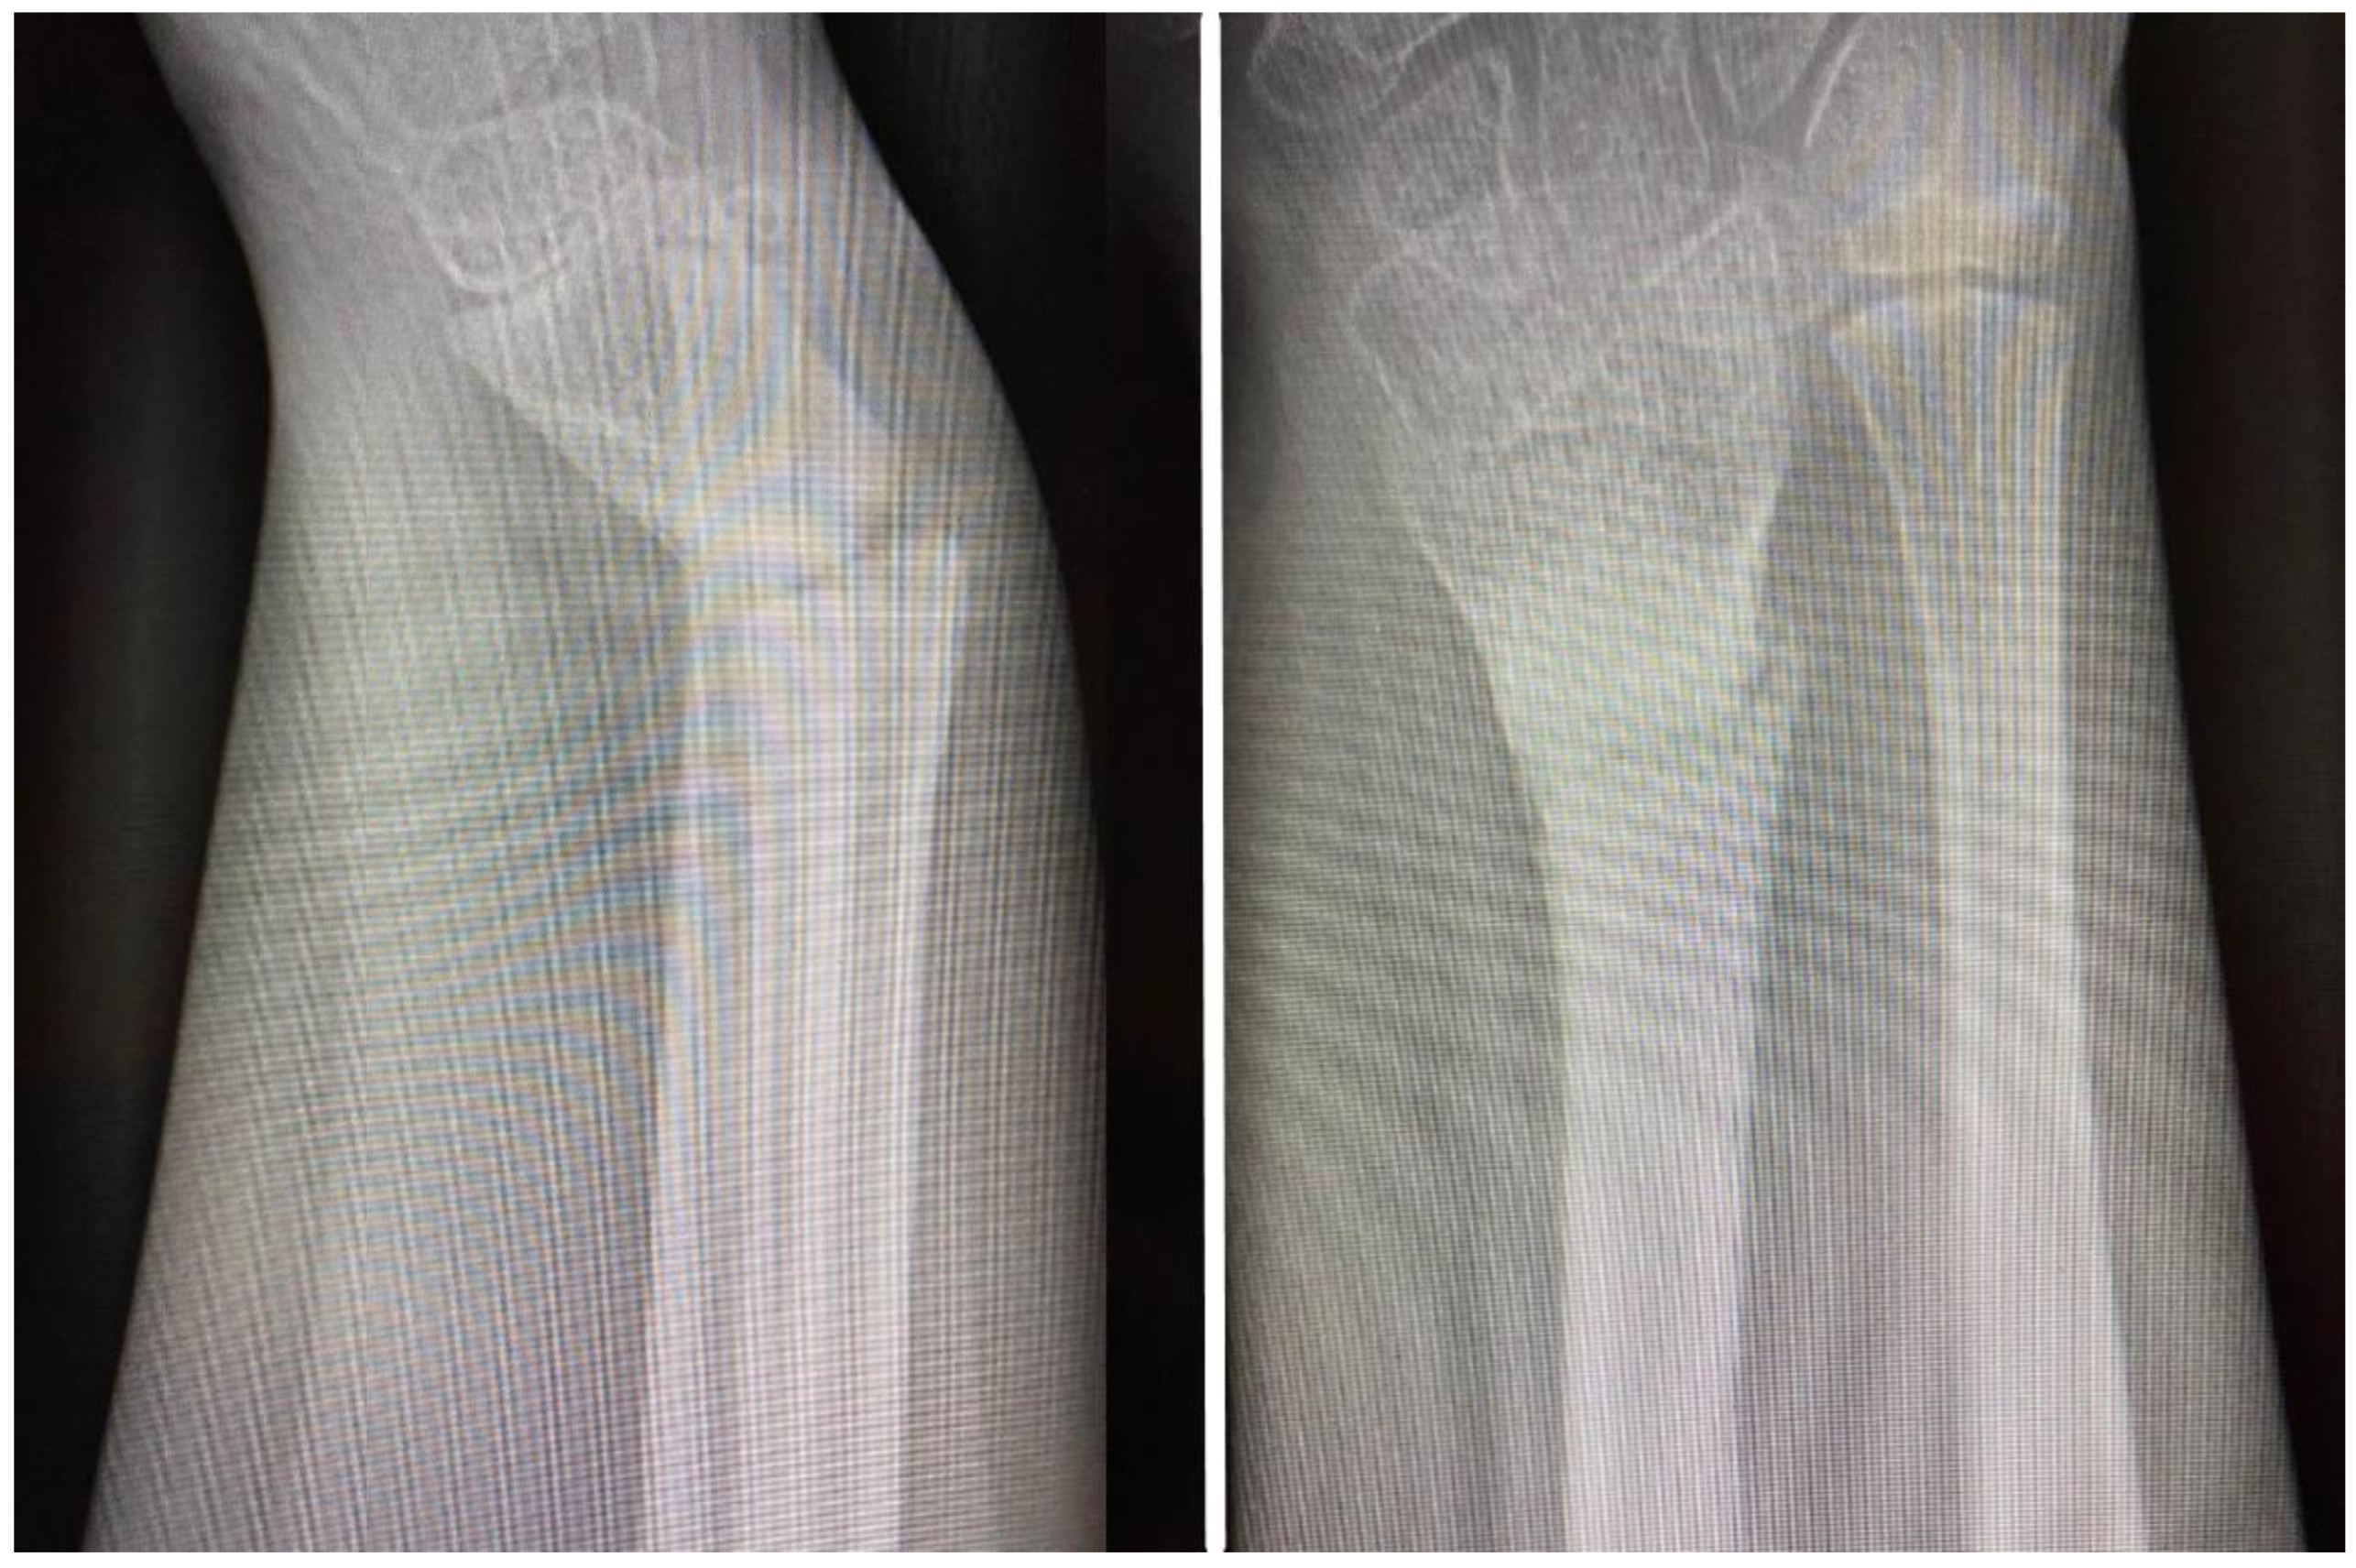

Post-operatively, the patient was immobilized in a cast splint for dressing protection, with gravitational drainage with the forearm in a sling, and presented for follow-up at two and four weeks. At 6 weeks, he was admitted for K-wire removal. However, after the removal of the K-wires the forearm became painful over the next few days, with progressive deformity of the distal forearm, which sent the patient back to the hospital in one week, and a radiological control exam was obtained. The fracture appeared with slight callus formation and volar angulation of the radius fracture. Because of the radiological aspect suggesting callus formation, the patient underwent soft orthopedic manipulation with reduction and was placed in a splint for four weeks. At the end of the 4-week immobilization, the splint was removed and a radiological exam obtained (Figure 3). At this point, 10 degrees of volar angulation was considered acceptable and the patient was advised to mobilize the hand and wrist as tolerated. Bear in mind that here we were situated in week 11 in this case’s chronology. Recovery did not develop as expected as there was intermittent pain with movement, a lack of mobility progress and progressive recurrence of the distal forearm deformity.

Figure 3. AP and lateral views obtained at the end of four weeks’ immobilization, demonstrating 10 degrees of volar angulation, which was considered acceptable at this point, but with inadequate callus formation.